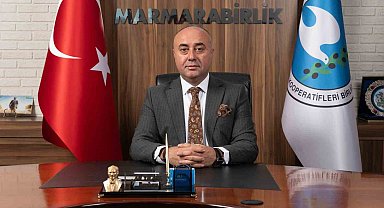

Konu ile ilgili bilgilendirmelerde bulunan Diyarbakır Memorial Hastanesinde Kardiyoloji Bölümünden Doç. Dr. Mesut Aydın hastaların genç yaşta kalp krizi şikayeti ile hastanelere başvuru yaptıklarını belirtti. Doç. Dr. Aydın, "Genç yaşta artık kalp krizlerini görebiliyoruz çünkü günümüzde maalesef herkeste çok fazla stres var. Beslenme şartları sağlıklı değil, özellikle ailede kalp rahatsızlığı olan kişilerin kalp krizi erken yaşta geçirme ihtimali var ve bunu bilmek lazım. Beklenmedik herhangi bir şikayet özellikle göğüs ağrısı, göğüste yanma, kollarda ağrı bunların dışında baş dönmesi, göz kararması, bayılma hissi, nefes darlığı, çabuk yorulma gibi şikayetler de varsa kişi muhakkak bir kardiyoloji uzmanına muayene olması gerekir'' dedi.

40 yaşından sonra herkesin bir kalp krizi geçirme ihtimalinin olduğunu kaydeden Doç Dr. Aydın, "Muhakkak yılda en az bir defa kardiyoloji muayenesi olunması gerekir. 45 yaşındaki hastamız göz kararması, baş dönmesi nedeniyle hastanemiz acilinde başvurmuş yapılan tetkikler normal çıkmıştı. Hastamız yaklaşık 3 yıl önce kalp krizi geçirmiş, stent takılmış. Kan değerleri normal çıkmış olmasına rağmen kalp krizini düşündüren şikayetlerinin olması nedeniyle anjiyo yapılmasına karar verdik ve bunun sonucunda kalbin en önemli komşu iki damarın çatal bölgesinde tıkalı olduğunu gördük. El bileğinden kısa sürede yaklaşık bir saat süren bir işlemle damarlar sağlıklı bir şekilde açıldı. Şu an hastamızı sağlıklı bir şekilde taburcu ettik" diye konuştu.